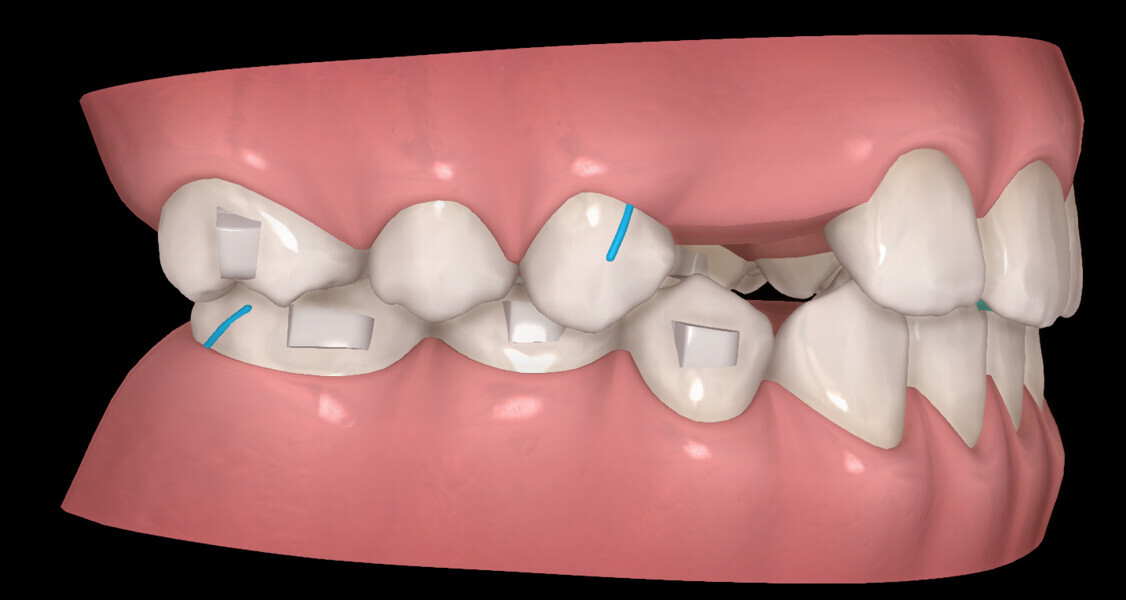

The digital treatment plan (ClinCheck) provided 18 aligners in each arch. The treatment objectives were focused on aligning and levelling the mandibular arch without excessively proclining the mandibular incisors, in order to control the Class III skeletal malocclusion by means of interproximal reduction and slicing of tooth #85. In the maxillary arch, the treatment plan focused on space creation for tooth #13 by distal rotation of the maxillary right molar and mesialisation of the maxillary right lateral incisor simultaneously to centre the midlines. Class II elastics were planned to control distal movement on the right side, and triangular elastics on the high canine were planned on the left side with button cutouts for the aligners. Lateral and posterior maxillary torque were planned to be close to 0° to achieve wider arch design and ideal intercuspation. No digital over-engineering was planned in the set-up, and lingual attachments according to personal preference were placed in the maxillary arch for aesthetic and biomechanical reasons (Figs. 15–19). Eruption compensation for tooth #13 was employed. Because of the age of the patient, the aligners were changed every seven days over the treatment period of less than five months.

At the end of the first stage of aligner treatment (Figs. 20–24), the auxiliary phase began with the bonding of two MTAs on the maxillary right premolars. A 0.016-in Australian archwire, shaped into a cantilever configuration, was then inserted into the MTAs, and a cutout was created on the final aligner. To prevent rotation, the archwire was cinched distal to tooth #15 and the cinch covered with composite.